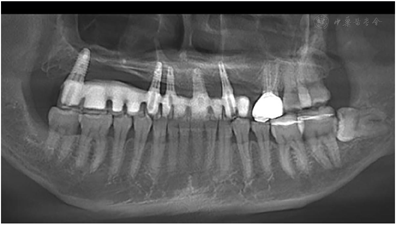

全口曲面断层片示16-25牙缺失(图3)。标准头颅侧位X线片以及头影测量分析结果显示上颌牙槽骨水平向骨缺损伴骨性反颌(图4)。CT结果显示上颌缺牙区牙槽骨缺损,骨性反颌。上颌16牙位窦嵴距离约1 mm,上颌前牙区牙槽骨高度不足7 mm,双侧下颌角肥大,呈方脸形态(图5)。

X线片和颌面CT检查发现双侧下颌角肥大、上颌骨重度骨缺损。

上颌骨植骨术后半年,伤口愈合良好。完善影像学检查和头影测量分析,按照治疗方案进行Ⅱ期正颌手术纠正骨性反he(牙合)。数字化虚拟方案如下,上颌骨Le Fort I型截骨前徙3mm,下颌骨矢状劈开术后退2mm(图7)。